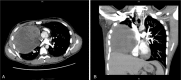

Germ cell tumors (GCTs) represent a well-recognized group of heterogeneous neoplasms with diverse clinical, histopathological, diagnostic, and prognostic characteristics. We present a rare case of a locally aggressive, chemotherapy-resistant immature mediastinal teratoma with a peculiar histological finding of a multilineage somatic-type malignant degeneration. A 21-year-old male patient presented with a 3-week history of persistent, blood-tinged productive cough and shortness of breath. A contrast-enhanced computed tomography (CT) scan of the chest showed a heterogeneous mass occupying the right hemithorax and abutting on adjacent structures. CT-guided biopsy was consistent with immature teratoma. Combination chemotherapy with bleomycin, etoposide, and cisplatin was initiated, albeit without success; the mass showed interval progression in size, and surgical resection through clamshell incision was performed. Histological assessment of the resected mass confirmed the diagnosis of immature teratoma and revealed an extensive multilineage malignant differentiation into sarcomatous, carcinomatous, and melanomatous components. The patient underwent an uneventful recovery but presented 2 months later with extensive liver and bone melanomatous metastases. In this report, relevant findings from the literature are also highlighted. Despite being exceptionally rare, such tumors carry poor prognosis. Understanding the clinicopathological characteristics and biological behavior of such tumors may provide an insight into interventions tailored to improve the otherwise dismal disease outlook.